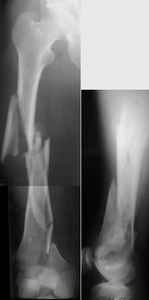

1. Percutaneous nailing is truly minimally invasive technique, but, unfortunately, nails are not reliable in many hands.

Attached are few examples from our Hospital:

A. Difficult reductions, even in retrograde nailing (my preference, easier control of "small" distal fragment) and it is much, much harder to do it anterograde (Alex, do you have one good case in your collection of anterograde nailing in very distal fractures - as you have suggested that I

should have done it in my previously posted case?

Malpositioning is much too common (recurvatum, varus - valgus).

B. Fixation loosening: distal cutting of the nail, non-unions do happen (cases attached).

Locking Plating has more distal screws than any nail, fixed angles and provides much better fixation, especially in osteoporotic bone.

I presented a series of ~25 such cases at EuroTrauma'2004. Many cases were discussed here. I attach am example. Look also recent cases at http://www.hwbf.org/hwb/conf/alex58/scfx.htm,